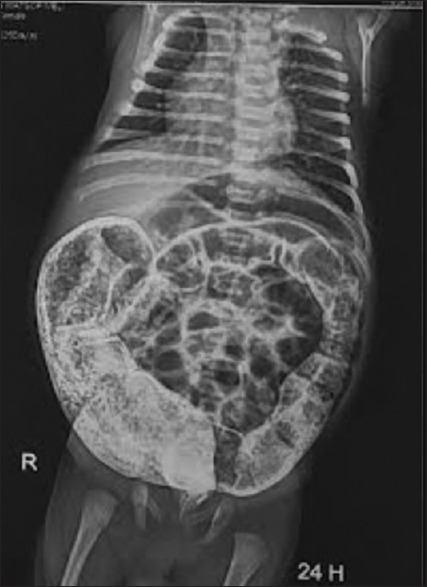

Results: Fifty two patients with a mean age of 18 months at the time of surgery. The male pre dominance was remarkable. The mean duration of the surgery was 2 h and a half hours. The surgical indication was based on the history, clinical findings and on the contrast enema (transition zone) with a 24 h film (prolonged contrast evacuation) and calculation of the rectosigmoid index (<1). With a mean follow up of 16 months, the morbidity was dominated by soiling, anastomotic strictures and enterocolitis. The mortality in one case was related to a post operative enterocolitis that was not amenable to resuscitation.